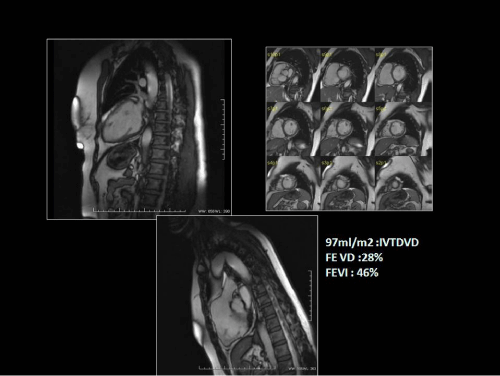

Figure 5: True fast imaging with steady-state precession sequence in two chamber (up-left), short axis (up-right), and right ventricle outflow tract (down) in a patient with a biventricular dilated cardiomyopathy.